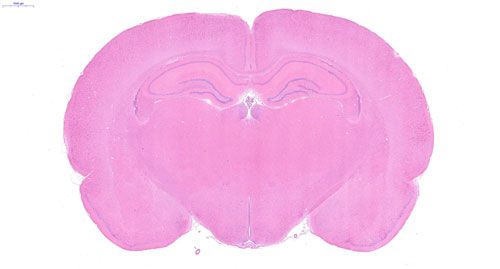

实验结果展示:

大鼠脑 普通切片扫描